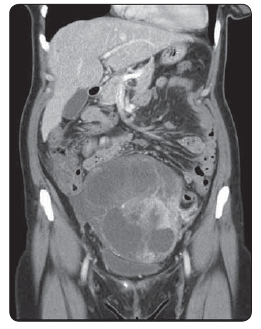

50letá pacientka, dosud interně nestonající, bez onkologické rodinné anamnézy, byla přijata na GPK FN Plzeň pro měsíc trvající bolesti břicha. Pro nález cystického útvaru na levém ovariu byla provedena hysterektomie s oboustrannou adnexektomií. Histologie útvaru vycházejícího z appendixu a prorůstající do ovaria byla IHC pozitivní na AE1/ 3 a chromogranin. V druhé době byla provedena pravostranná hepatektomie pro metastatické postižení. U pacientky bylo v plánu podání systémové léčby, ale v první době bylo nutné dořešení nálezu megaureteru vpravo. Indikována nefrektomie. Nově se objevili potíže charakteru exophtalmu a deprese bulbu levého oka. Provedeno kontrolní CT orbity s nálezem expanze charakteru metastázy v levé očnici. Následně provedeno CT břicha s nálezem masivní generalizace v průběhu colon ascendens a hepatálního ohbí, lymfatických uzlin retroperitonea, podél pánevních svazků vlevo a na resekční ploše jater. Při maximálních obtížích způsobených metastázou v orbitě byla indikována konkomitantní chemoradioterapie. Zahájena systémová léčba kapecitabinem a pro karcinoidové projevy zahájena léčba lanreotidem. Přes provedenou léčbu lokální nález progredoval a objevily se bolesti, které si vyžádaly léčbu opiáty. Pacientka umírá sedm měsíců od operace.